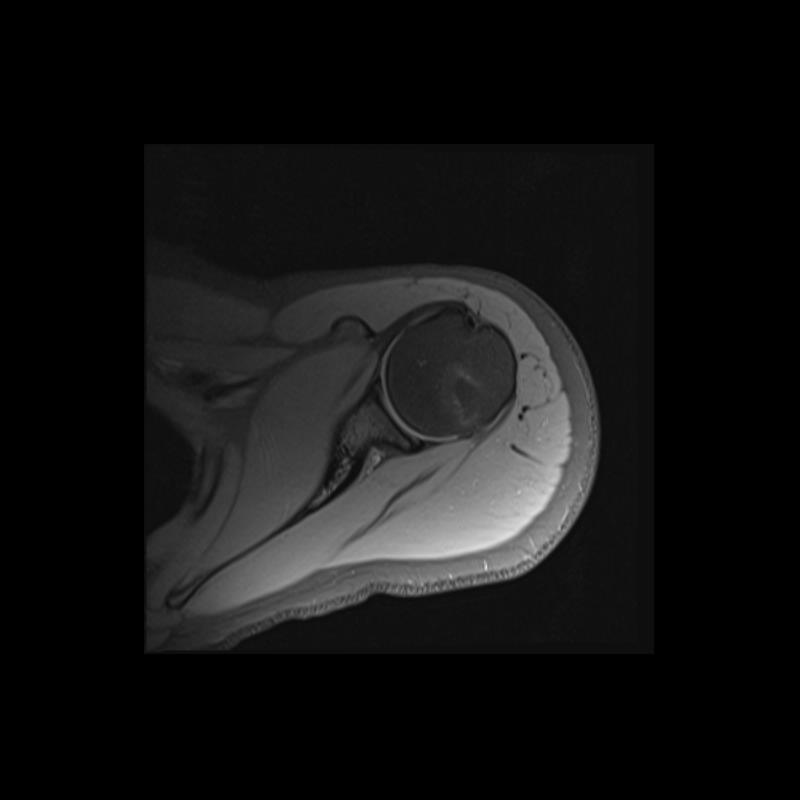

Shoulder MRI Anatomy